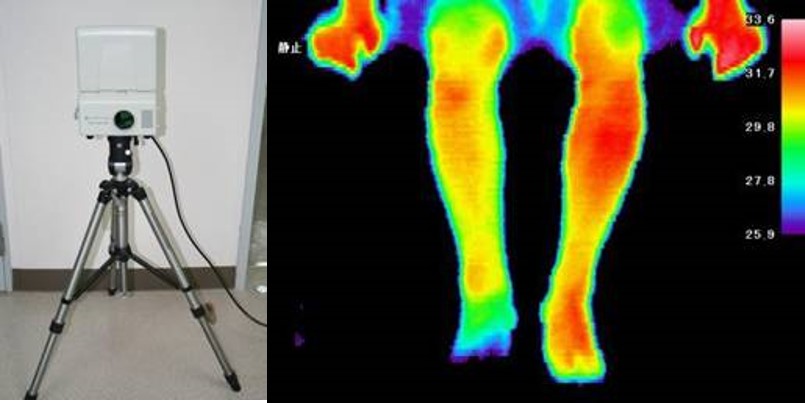

6.サーモグラフィー:サーモグラフィーは皮膚の温度を赤外線カメラで測定して、交感神経の働きや、炎症があるかをしらべる検査です(図3)。

図3:サーモグラフィ